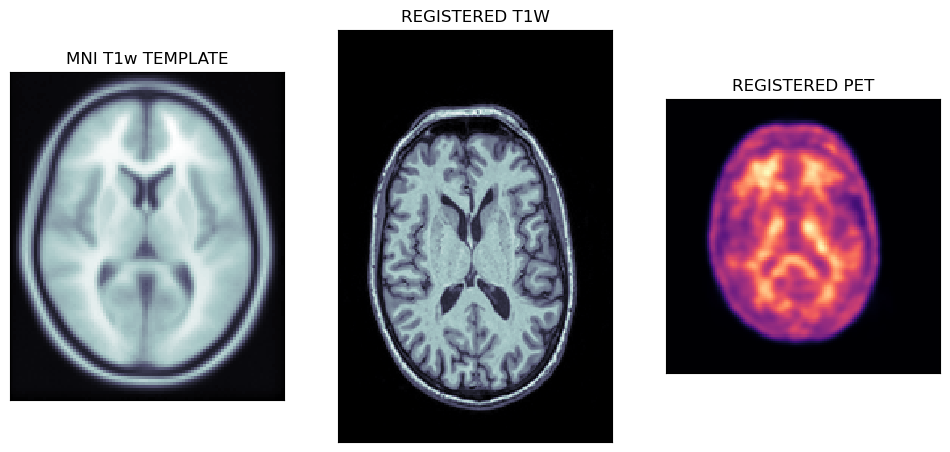

Viewing affine registered MRI and PET images

The first output of the CL pipeline are the registrations of T1w MRI image to the MNI template followed by the registration of PET to the MNI registered MRI image.

axs[0].set_title('MNI T1w TEMPLATE')

axs[1].set_title('REGISTERED T1W')

axs[2].set_title('REGISTERED PET')

The plots below show the MNI template with the registered MRI and PET images.